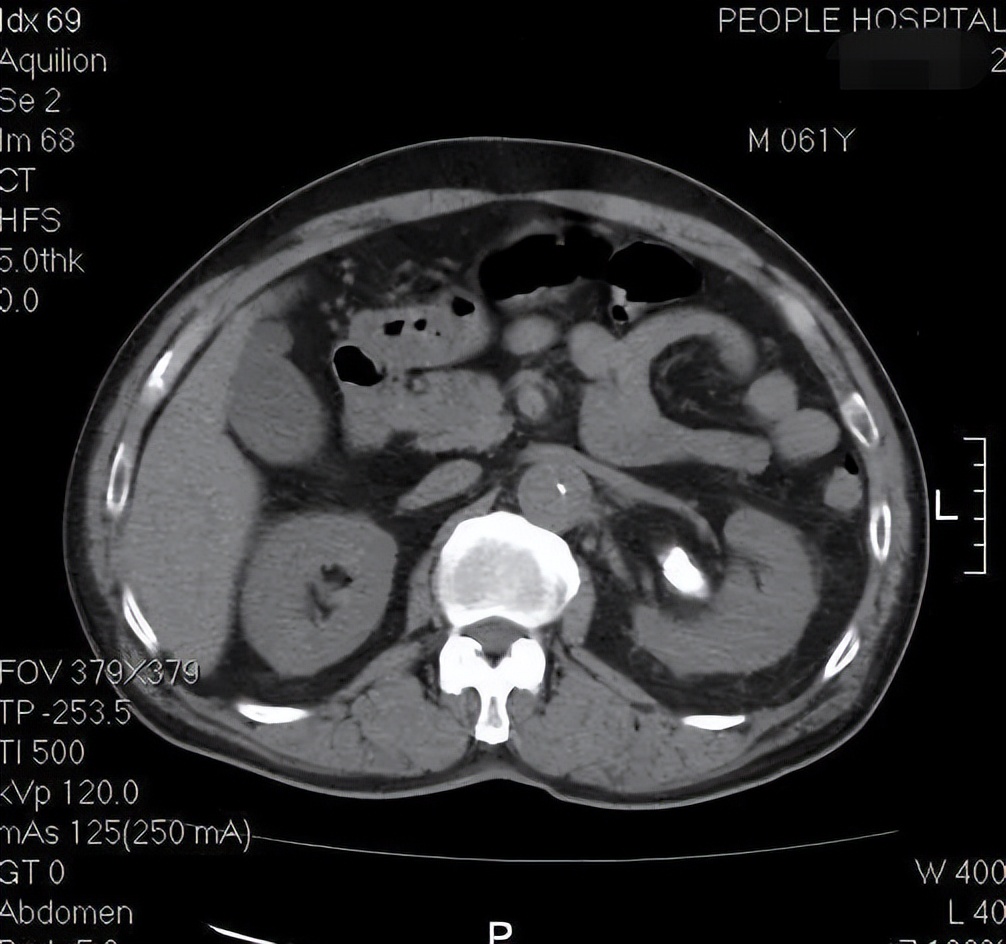

突然间,医生注意到患者的主动脉钙化斑有明显的内移!

所谓的主动脉钙化斑内移,一般是因为血管弹力降低或血管壁受损引起的。正常情况下,血管钙化影应该在血管壁上,但是此时的钙化斑竟然出现在了血管内部!

因为从增强CT可以清楚的看到,可见患者的主动脉内真假腔形成,这是典型的主动脉夹层啊!

仔细一点可以看到,左肾动脉开口于假腔,导致左肾动脉缺血,患者左肾的肾绞痛可能就是因为这个原因!

而平扫CT上的钙化影内移,表明主动脉夹层在此处已经有开始撕裂的征象!